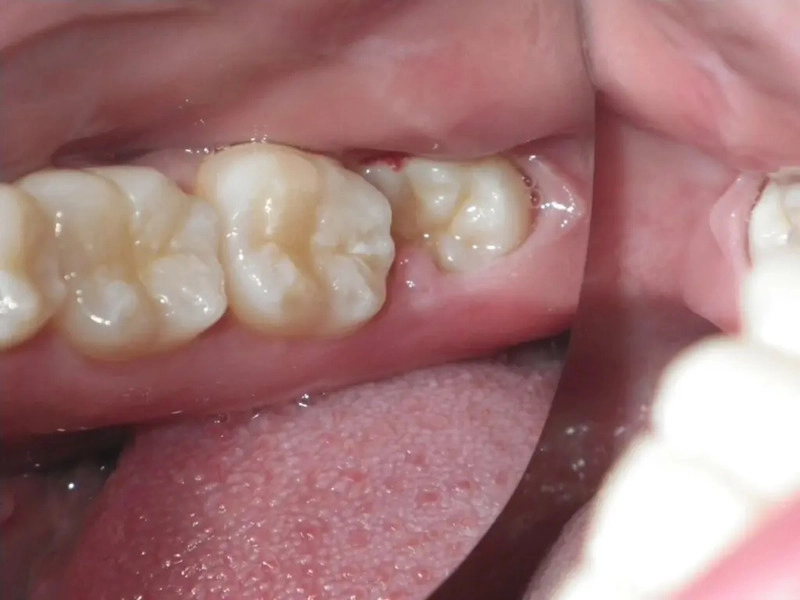

Răng mọc khó: Các trường hợp răng cắm sâu, xiên vẹo, mọc ngược, mọc lệch, hoặc mọc bất thường gây tổn thương cho các răng số 7 xung quanh.